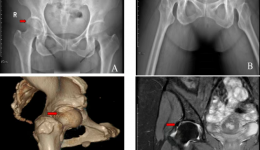

近日,我院运动医学科成功为一名被髋部疼痛困扰半年的患者A女士,实施了一项高难度的微创手术——髋关节镜下盂唇重建术,助她摆脱疼痛,重拾正常生活。病情背景A女士是一位热爱运动的中年女性。半年来,她的右髋部总是疼痛,活动不便,近两个月情况...

• 我院完成一例关节镜下儿童胫骨平台骨折手术

近日,我院小儿骨科联合运动医学科为一位12岁的胫骨平台骨折女童完成关节镜下手术。患儿入院后,小儿骨科医生为其完善了检查,发现患儿为左膝胫骨平台骨折,CT显示其胫骨平台塌陷0.5cm。儿童胫骨平台骨折比较罕见,治疗起来也比较棘手。因患儿年幼...